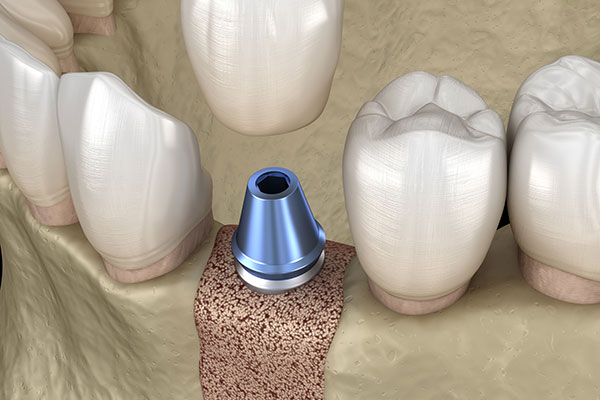

インプラント治療には、埋入部位に十分な骨の量が必要不可欠です。そのため、骨が足りないことを理由に「治療はできない」と診断されるケースも少なくありません。 しかし当院では、骨を増やす「GBR(骨再生誘導法)」や骨移植といった高度な技術を用いることで、そうした難症例にも対応可能です。骨の薄い部位に人工骨や自家骨を補填し、土台となる十分な厚みと幅を再建します。さらに再生療法(CGF/PRP)を併用して治癒を促進させることで、これまで「インプラントは難しい」と諦めていた方でも、可能な限り理想の治療が受けられるよう最善を尽くします。

二次手術

インプラントが骨としっかり結合したことを確認後、歯ぐきをわずかに切開して、被せ物の土台となる「アバットメント」を装着します。